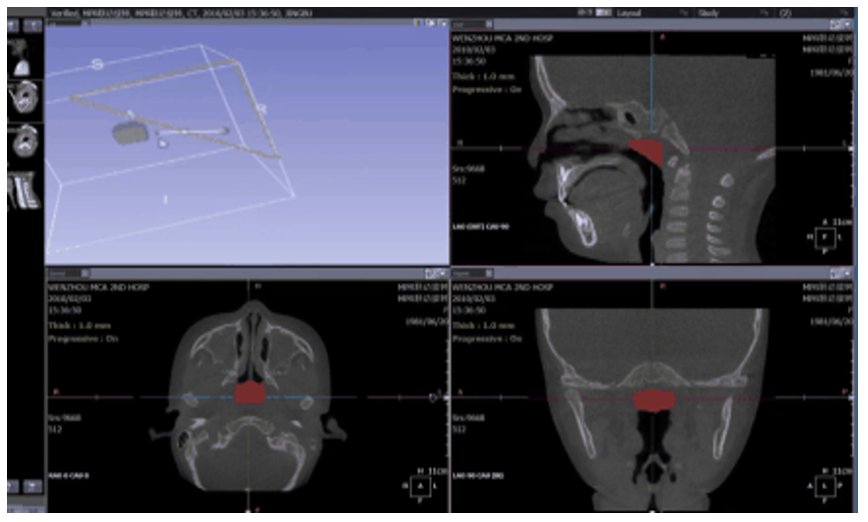

该解决方案当前主要针对小儿腺样体肥大、咽喉上气道堵塞疾病、阻塞性睡眠呼吸暂停综合征等咽喉疾病,使用昇思MindSpore AI框架,以3DUNet为基础构建了一个新的弱边界分割模型,通过华为云ModelArts进行模型的训练,在诊疗的过程中进行模型推理,实现在术前进行病变区域的精准识别和术后创口的预测规划,从而保证相关咽喉手术精准安全高效完成。

在构建模型的基础上,使用了昇腾910上进行训练和推理,训练了5000epochs,在腺样体分割的任务上达到91.49%的精度,超过现在的SOTA模型。并且设计了可视化的页面,使用云端算力进行推理,方便医生进行一个明确的术前规划和预测。